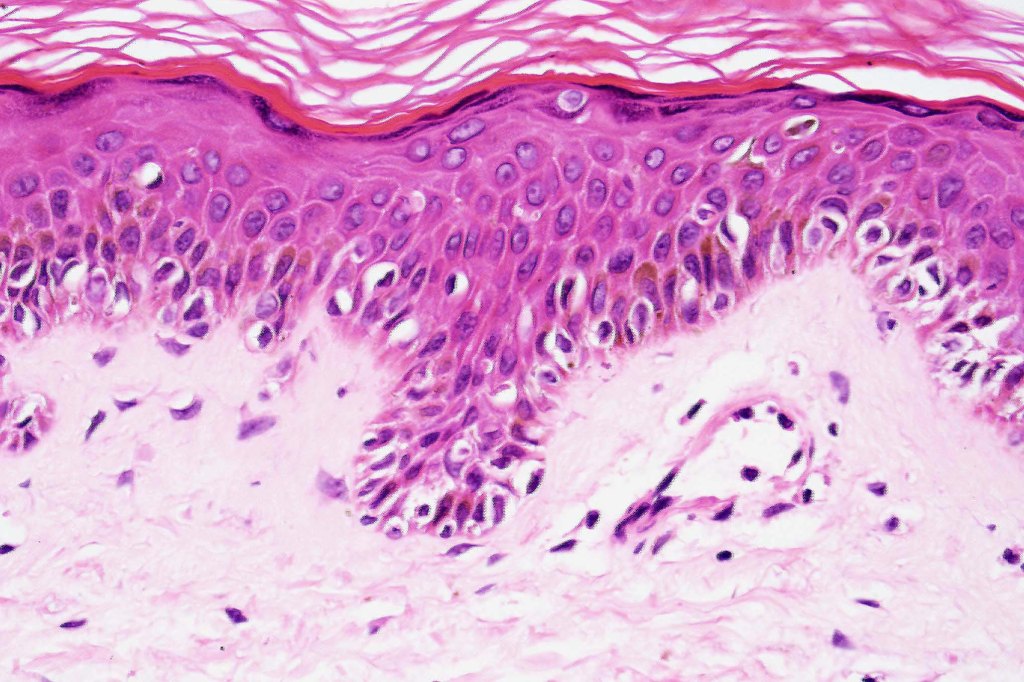

- A broad lentiginous proliferation of atypical melanocytes unasscoiated with any loss of the rete ridges

2. Melanocytes generally small, epithelioid (rather than spindled) with either vesicular nuclei and prominent nucleoli or are hyperchromatic.

3. The cells can be present singly, in short pallisades or can extend along a large section of epidermis

7. Fibroplasia not seen and elastosis is either mild or absent